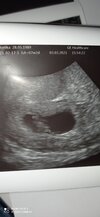

Mamy ❤️ i crl 1cm🥰🥰🥰 zdjęcie nie do końca dokładne. Termin porodu wg OM 19.10 wg USG 18.10 więc to samo😁 mąż ze mną był na USG więc wogole super🥰🥰

Załączniki

• IMG_20210303_175958.jpg

IMG_20210303_175958.jpg

691,2 KB · Wyświetleń: 113